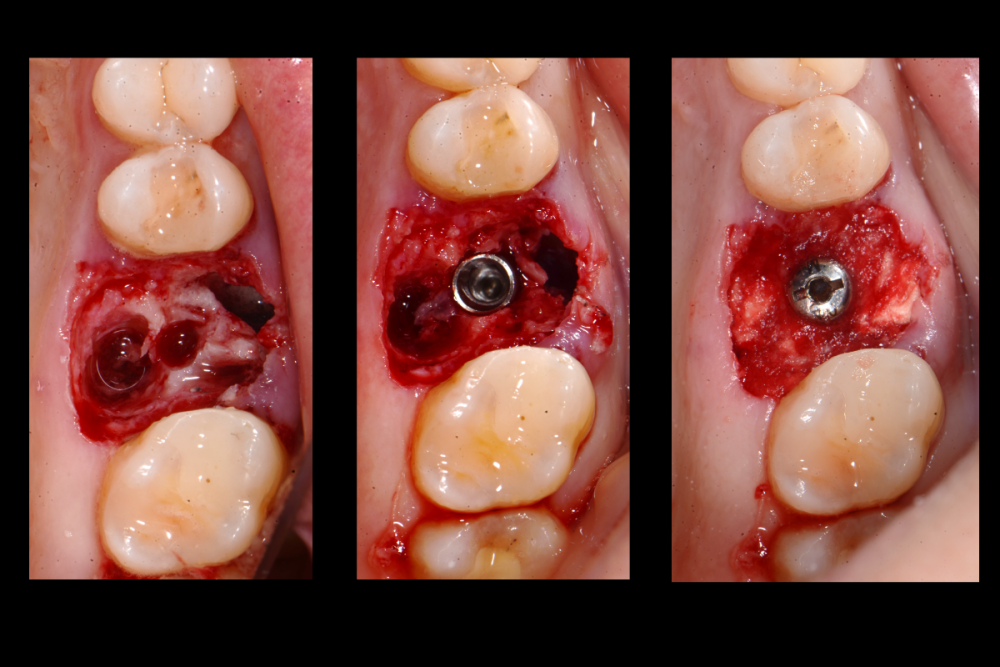

Карен Аванесов Опубликовано 10 ноября, 2021 Автор Поделиться Опубликовано 10 ноября, 2021 Придерживаясь правил форума, второе сообщение содержащее фотоматериал выдержанно в лучших традициях русской словестности, без сквернословия и непонятных иностранных слов, без применения шовного материала, широких формирователей десневой манжеты, без мягкотканной и прочей аугментации (наращивание костей что то все же не звучит прилично)), а самое главное, время затраченное на всю операцию 60 минут (имплантаты на нижней челюсти установил по лазерной технологии, без разрезов, Лазер - сила!). Время ожидания до ортопедического этапа 3 месяца. 6 1 Ссылка на комментарий

Марья Моревна Опубликовано 13 ноября, 2021 Поделиться Опубликовано 13 ноября, 2021 А что это такое кругленькое виднеется в лунке небного корня на самом левом из трех снимков над панорамой? 1 Ссылка на комментарий

Карен Аванесов Опубликовано 14 ноября, 2021 Автор Поделиться Опубликовано 14 ноября, 2021 13.11.2021 в 08:55, annda сказал: У инженера гиперболоид был, однако Не претендую на раскрытие секретов, видимо, что- то сакральное. Анна Анатольевна, в данном контексте, упоминание лазера, не более чем гипербола. Улыбайтесь чаще, Вам идет улыбка) 13.11.2021 в 20:19, Марья Моревна сказал: А что это такое кругленькое виднеется в лунке небного корня на самом левом из трех снимков над панорамой? А Вы Марья Моревна глазастенькая! Это воздушный пузырь, там две перфорации синуса, после удаления кисты. Ссылка на комментарий

Карен Аванесов Опубликовано 14 ноября, 2021 Автор Поделиться Опубликовано 14 ноября, 2021 (изменено) 13.11.2021 в 20:19, Марья Моревна сказал: А что это такое кругленькое виднеется в лунке небного корня на самом левом из трех снимков над панорамой? Это некий цимус-изюминка, в этой работе Изменено 14 ноября, 2021 пользователем Карен Аванесов Ссылка на комментарий